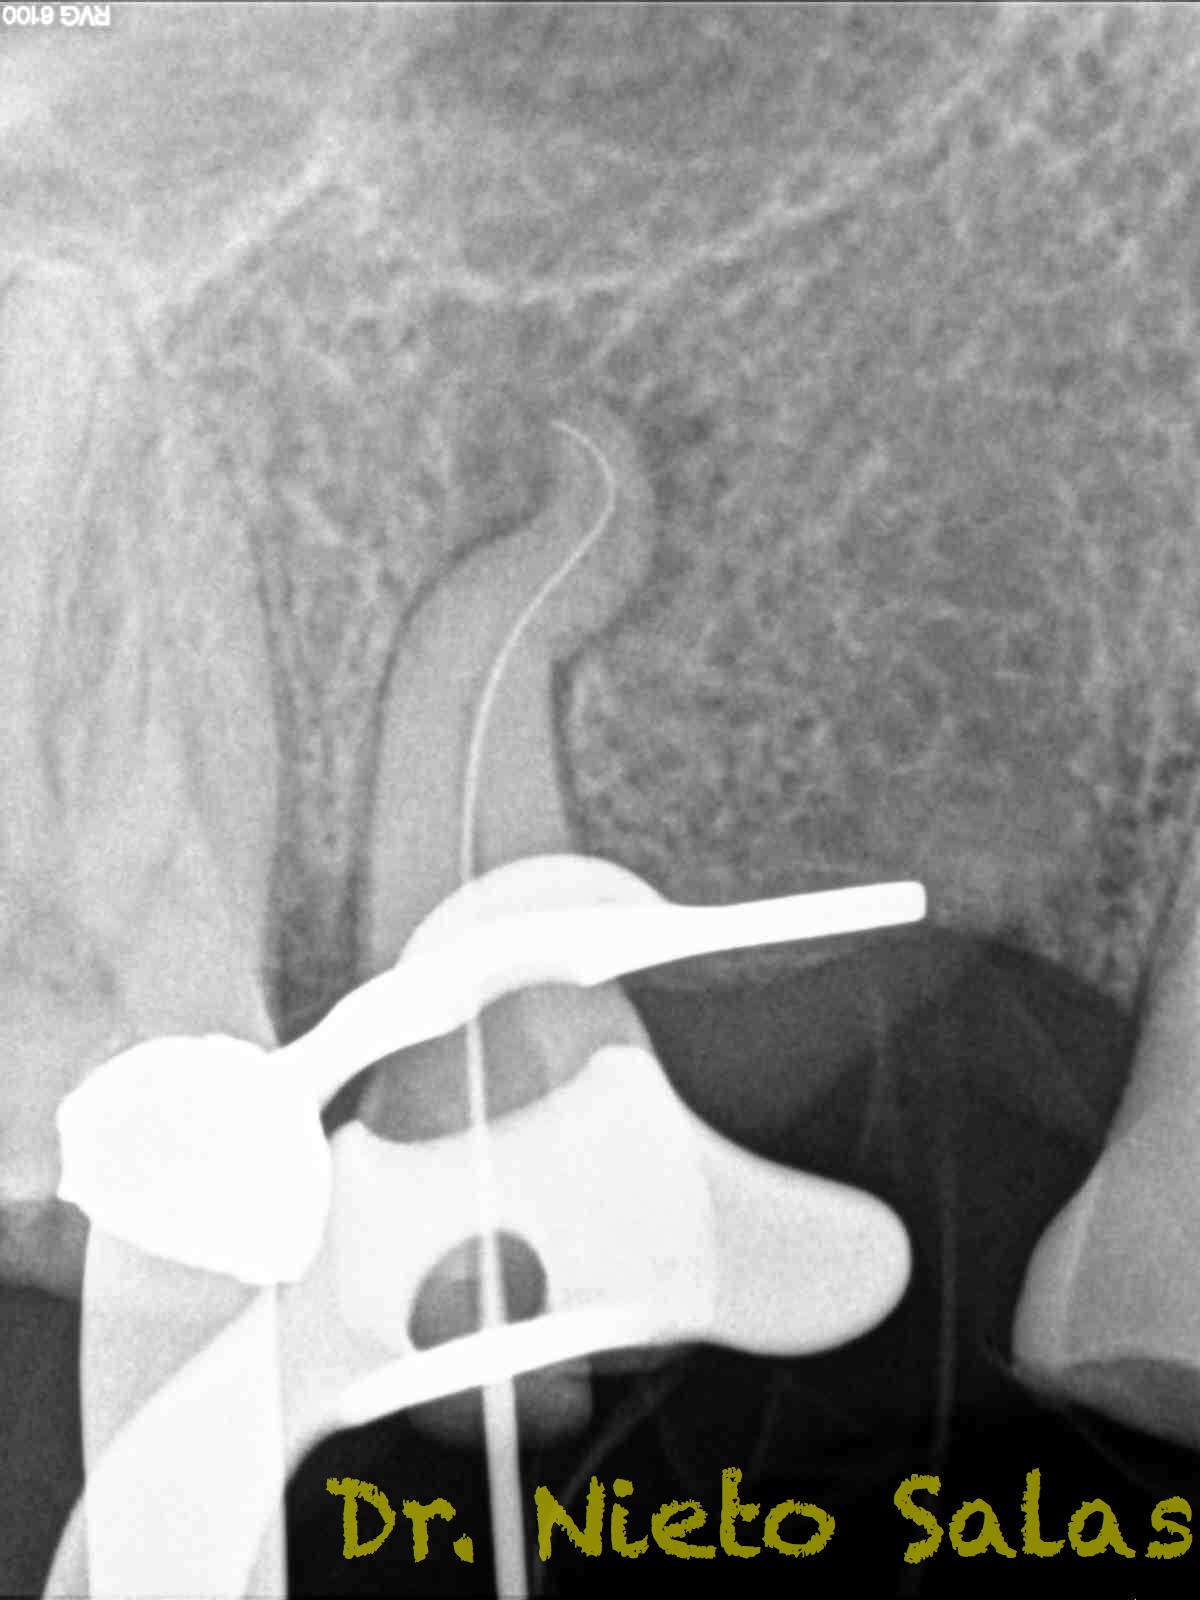

Se nos presenta en la clínica un par de casos de características similares, con lo cual las hemos tratado igual:

Ante estas situaciones, lo que no debemos es intentar llegar a la zona apical rápido, primero prepararemos el tercio medio-coronal, pero sin perder la permeabilidad del conducto con limas de muy pequeños diámetro.

Una vez que tenemos la Long de trabajo, no debemos perderla, se recomienda mucha irrigación e intentaremos que nuestras limas trabajen en una superficie lo menor posible.